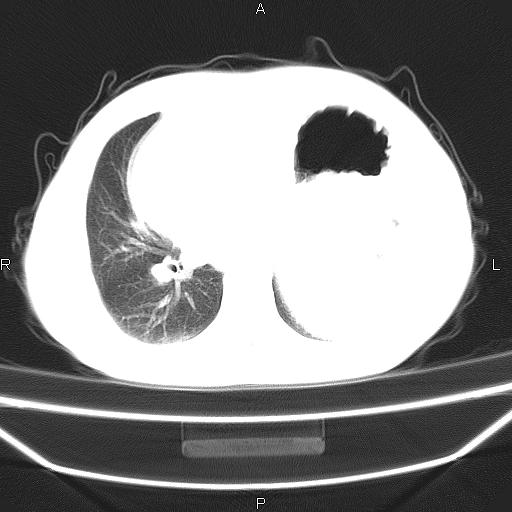

患者,男。50岁。近几日有咳嗽症状,无其他不适,既往病史无,考虑膈疝。请前辈们看看指导指导。

膈膨升,左下肺通气不良,膈肌好像还完整。

考虑左侧膈疝。

左侧膈疝。

符合隔膨升,膈肌较完整。